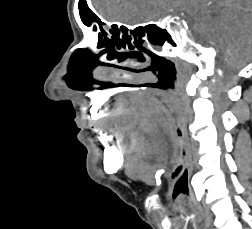

Одним из методов диагностики заболеваний носоглоточной области является мультиспиральная компьютерная томография. Методика предусматривает использование рентгеновского излучения. Благодаря различной способности тканей поглощать рентгеновские лучи и последующей цифровой обработке полученных данных, удается получить изображения исследуемой зоны в мельчайших подробностях. Рентгеновские лучи лучше всего поглощаются плотными тканями, такими как костная ткань, поэтому кости хорошо видны на снимках КТ.

При необходимости улучшения визуализации мягкотканных структур и особенно при подозрении на опухолевый процесс, применяется внутривенное болюсное контрастирование. Йодсодержащее контрастное вещество вводится пациенту в вену, после чего оно попадает в кровеносную систему и с током крови разносится по организму. Патологические очаги в большей степени накапливают контраст, что на снимках придает им детальность и яркие очертания на фоне окружающих здоровых тканей.

Инновационные цифровые приложения томографов позволяют получить снимки высокого качества и детализации, а также создать трехмерные реконструкции анатомической зоны исследования, что дает возможность рассмотреть пространственное расположение органов и патологических образований. КТ носоглотки с контрастом назначают при подозрении на рост новообразований, в случае хронического воспаления, при врожденных аномалиях строения носа и прилегающих к нему придаточных пазух.